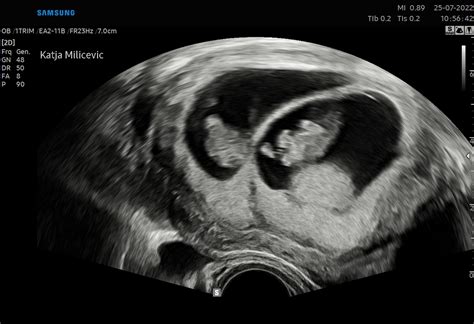

Nato opravimo ginekološki pregled, po potrebi tudi vaginalni pregled ali palpacijo materničnega vratu. Z ultrazvočnim pregledom, ki ga večinoma izvajamo z vaginalno sondo, potrdimo vitalnost nosečnosti v maternici in izključimo izvenmaternično nosečnost. Določimo število plodov ter pri večplodni nosečnosti določimo horionost in amnionost, kar je ključno za nadaljnje vodenje nosečnosti. Pregledamo tudi maternico in sosednje strukture, da izključimo morebitne nepravilnosti na jajčnikih, jajcevodih in v mali medenici.

Ob prvem pregledu ocenimo trajanje nosečnosti z meritvijo dolžine teme-trtica in določimo predvideni datum poroda. Če je prvi ultrazvočni pregled opravljen po 11. tednu, lahko opravimo tudi zgodnjo morfologijo ploda, kjer pregledamo osnovne organe, kot so glava, možgani, hrbtenica, želodec, sečni mehur, roke (preštejemo prste) in noge, izmerimo srčni utrip in ocenimo položaj posteljice. V primeru odstopanja med datumom zadnje menstruacije in ultrazvočno meritvijo za več kot 7 dni, se datum poroda prestavi glede na ultrazvočno meritev.

Ultrazvočne preiskave so nepogrešljiv del spremljanja nosečnosti, saj omogočajo vpogled v rast in razvoj ploda ter zgodnje odkrivanje morebitnih nepravilnosti. V sodelovanju s Porodnišnico Ljubljana opravimo dve ključni ultrazvočni preiskavi.

Prva ultrazvočna preiskava se opravi ob prvem pregledu v nosečnosti, kot je opisano zgoraj.

Vsem nosečnicam svetujemo tudi ultrazvočni pregled zgodnje morfologije ploda z merjenjem nuhalne svetline med 11. in 14. tednom nosečnosti. Ta pregled omogoča oceno tveganja za kromosomske nepravilnosti, kot so Downov sindrom (trisomija 21), Edwardsov sindrom (trisomija 18) in Patauov sindrom (trisomija 13). Izmeri se debelina nabrane tekočine v področju zatilja ploda (nuhalna svetlina), oceni se nosna kost in izmeri razdalja teme-trtica (CRL). Z meritvijo nuhalne svetline, starostjo nosečnice in srčno frekvenco ploda lahko odkrijemo približno 80 % kromosomskih napak, če pa se doda še dvojni hormonski test (DHT), se ta odstotek poveča na 90 %.